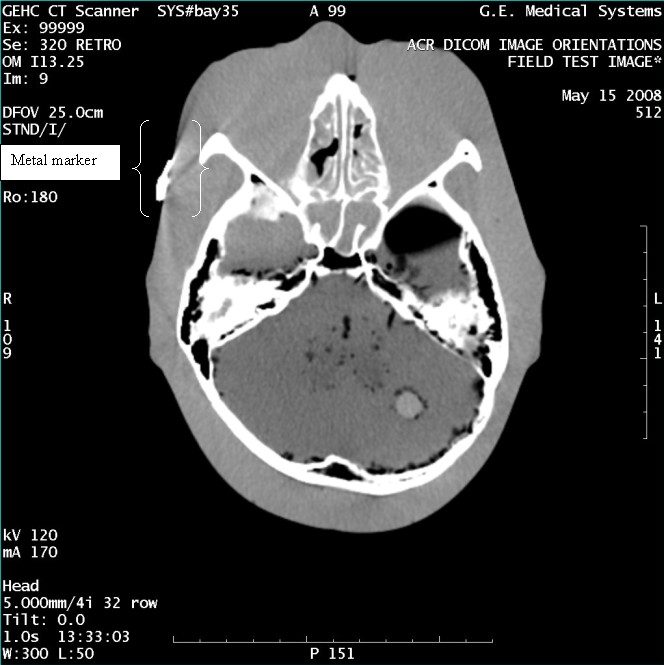

- With the support of the site personnel, examine the images sent

to the Review Station (i.e., 12 series, each with 1 image) and compare

their orientation to the images in this document.

- Each image contains a metal marker on the phantom's right cheek.

- Each image in this document contains a description of the expected

orientation of the metal marker (i.e. to prove Left and Right) as

well as the Posterior and Anterior orientation description.note:

The sample images included in this document use “R”, “L”, “P”, and “A” for “Right”, “Left”, “Posterior” and “Anterior” orientation. The Hospital Review Station may use a different style of annotation. The style used is not relevant to this procedure.

- Each image in this document has sufficient space to store the observed results for up to 4 Review Stations.

- Enter ‘Y’ in the space to indicate the observed result matches the expected.

- Enter ‘N’ in the space to indicate the observed result does not match the expected.

- Enter “NA” in the space if a column is not being used.

- Repeat for each destination.

Figure 5. Exam 99999, Series 320

Figure 6. Exam 99999, Series 322